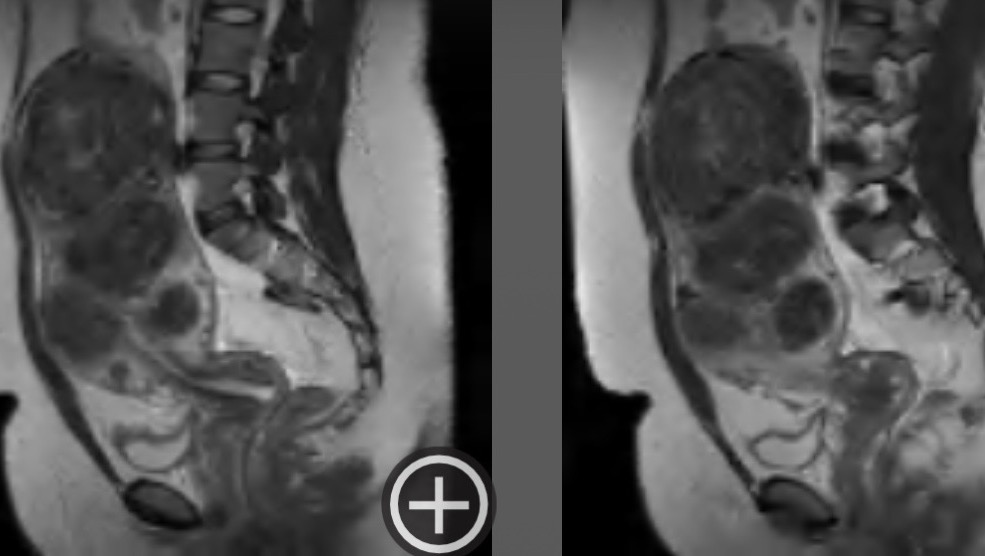

Uterine Fibroids are noncancerous growths of the uterus that are extremely common for Black women. Unfortunately, my pelvic sonogram showed a markedly enlarged uterus with 5 medium-sized fibroids and other smaller fibroids. (doctor informed me there’s 30+.) To give you an example of the sizes of my fibroids, they all vary between as small as a strawberry and as large as a grapefruit or small watermelon.

My doctors communicated that these fibroids have been living in me for roughly 9-10 years, and that one of my fibroids is the size of a 7-month-old child. So for that long, doctors throughout the years continued to ignore my symptoms and family history to the point where I managed to normalize and cope with the pain and symptoms I’ve felt. Knowing I’m about to feel like an entirely different person once they’re all removed has been very overwhelming. Please be patient with me. Thank you for reading and sharing. I genuinely appreciate all of your support, xo.